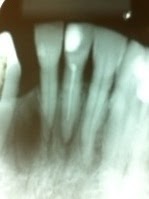

Caso clinico 1 ano proservação!

Caso clínico 1 ano proservação

Trauma -rizogêneze incompleta

Controle de infecção ca(oh)2 15 dias

Plug MTA e pino fibra vidro mesma sessão!!